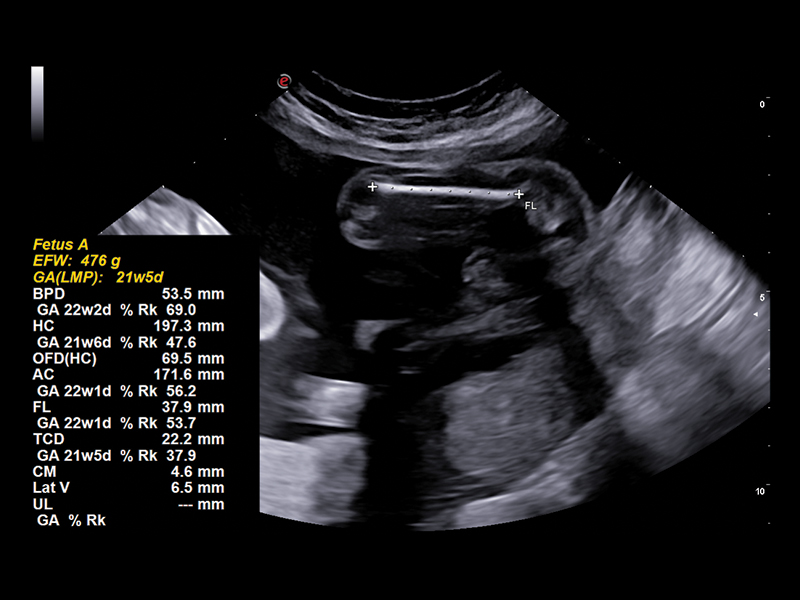

Streamlined A.I.-Assisted Workflow

In some ways, the study of fetal biometrics is the most challenging and important aspect of obstetric examinations. To speed up daily workflow without sacrificing the consistency and accuracy of the examination, Esaote has added AutoOB A.I. technology to all its systems. AutoOB is your ally in fetal biometrics assessment: once the plane of interest has been identified, it uses automatic recognition to suggest most of the standard biometric measurements, such as BPD, TCD, FL, AC and HC.